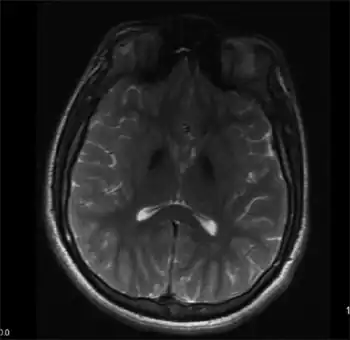

| Mitochondrial membrane protein-associated neurodegeneration-Symmetric, hypointense lesions in the globus pallidus, and substantia nigra | |

MPAN might be suspected with typical presentation and findings on MRI (Magnetic Resonance Imaging), these include evidence of iron deposition in the brain, particularly in the basal ganglia (globus pallidus and substantia nigra).[1][3] The diagnosis is confirmed by genetic testing identifying harmful variant(s) in C19orf12.[1]

Pathological findings in brains of people with MPAN include iron deposition and scarring in the globus pallidus, loss of neurons in the substantia nigra, and widespread Lewy bodies and spherical bodies from degenerating neurons.[1][3][6]